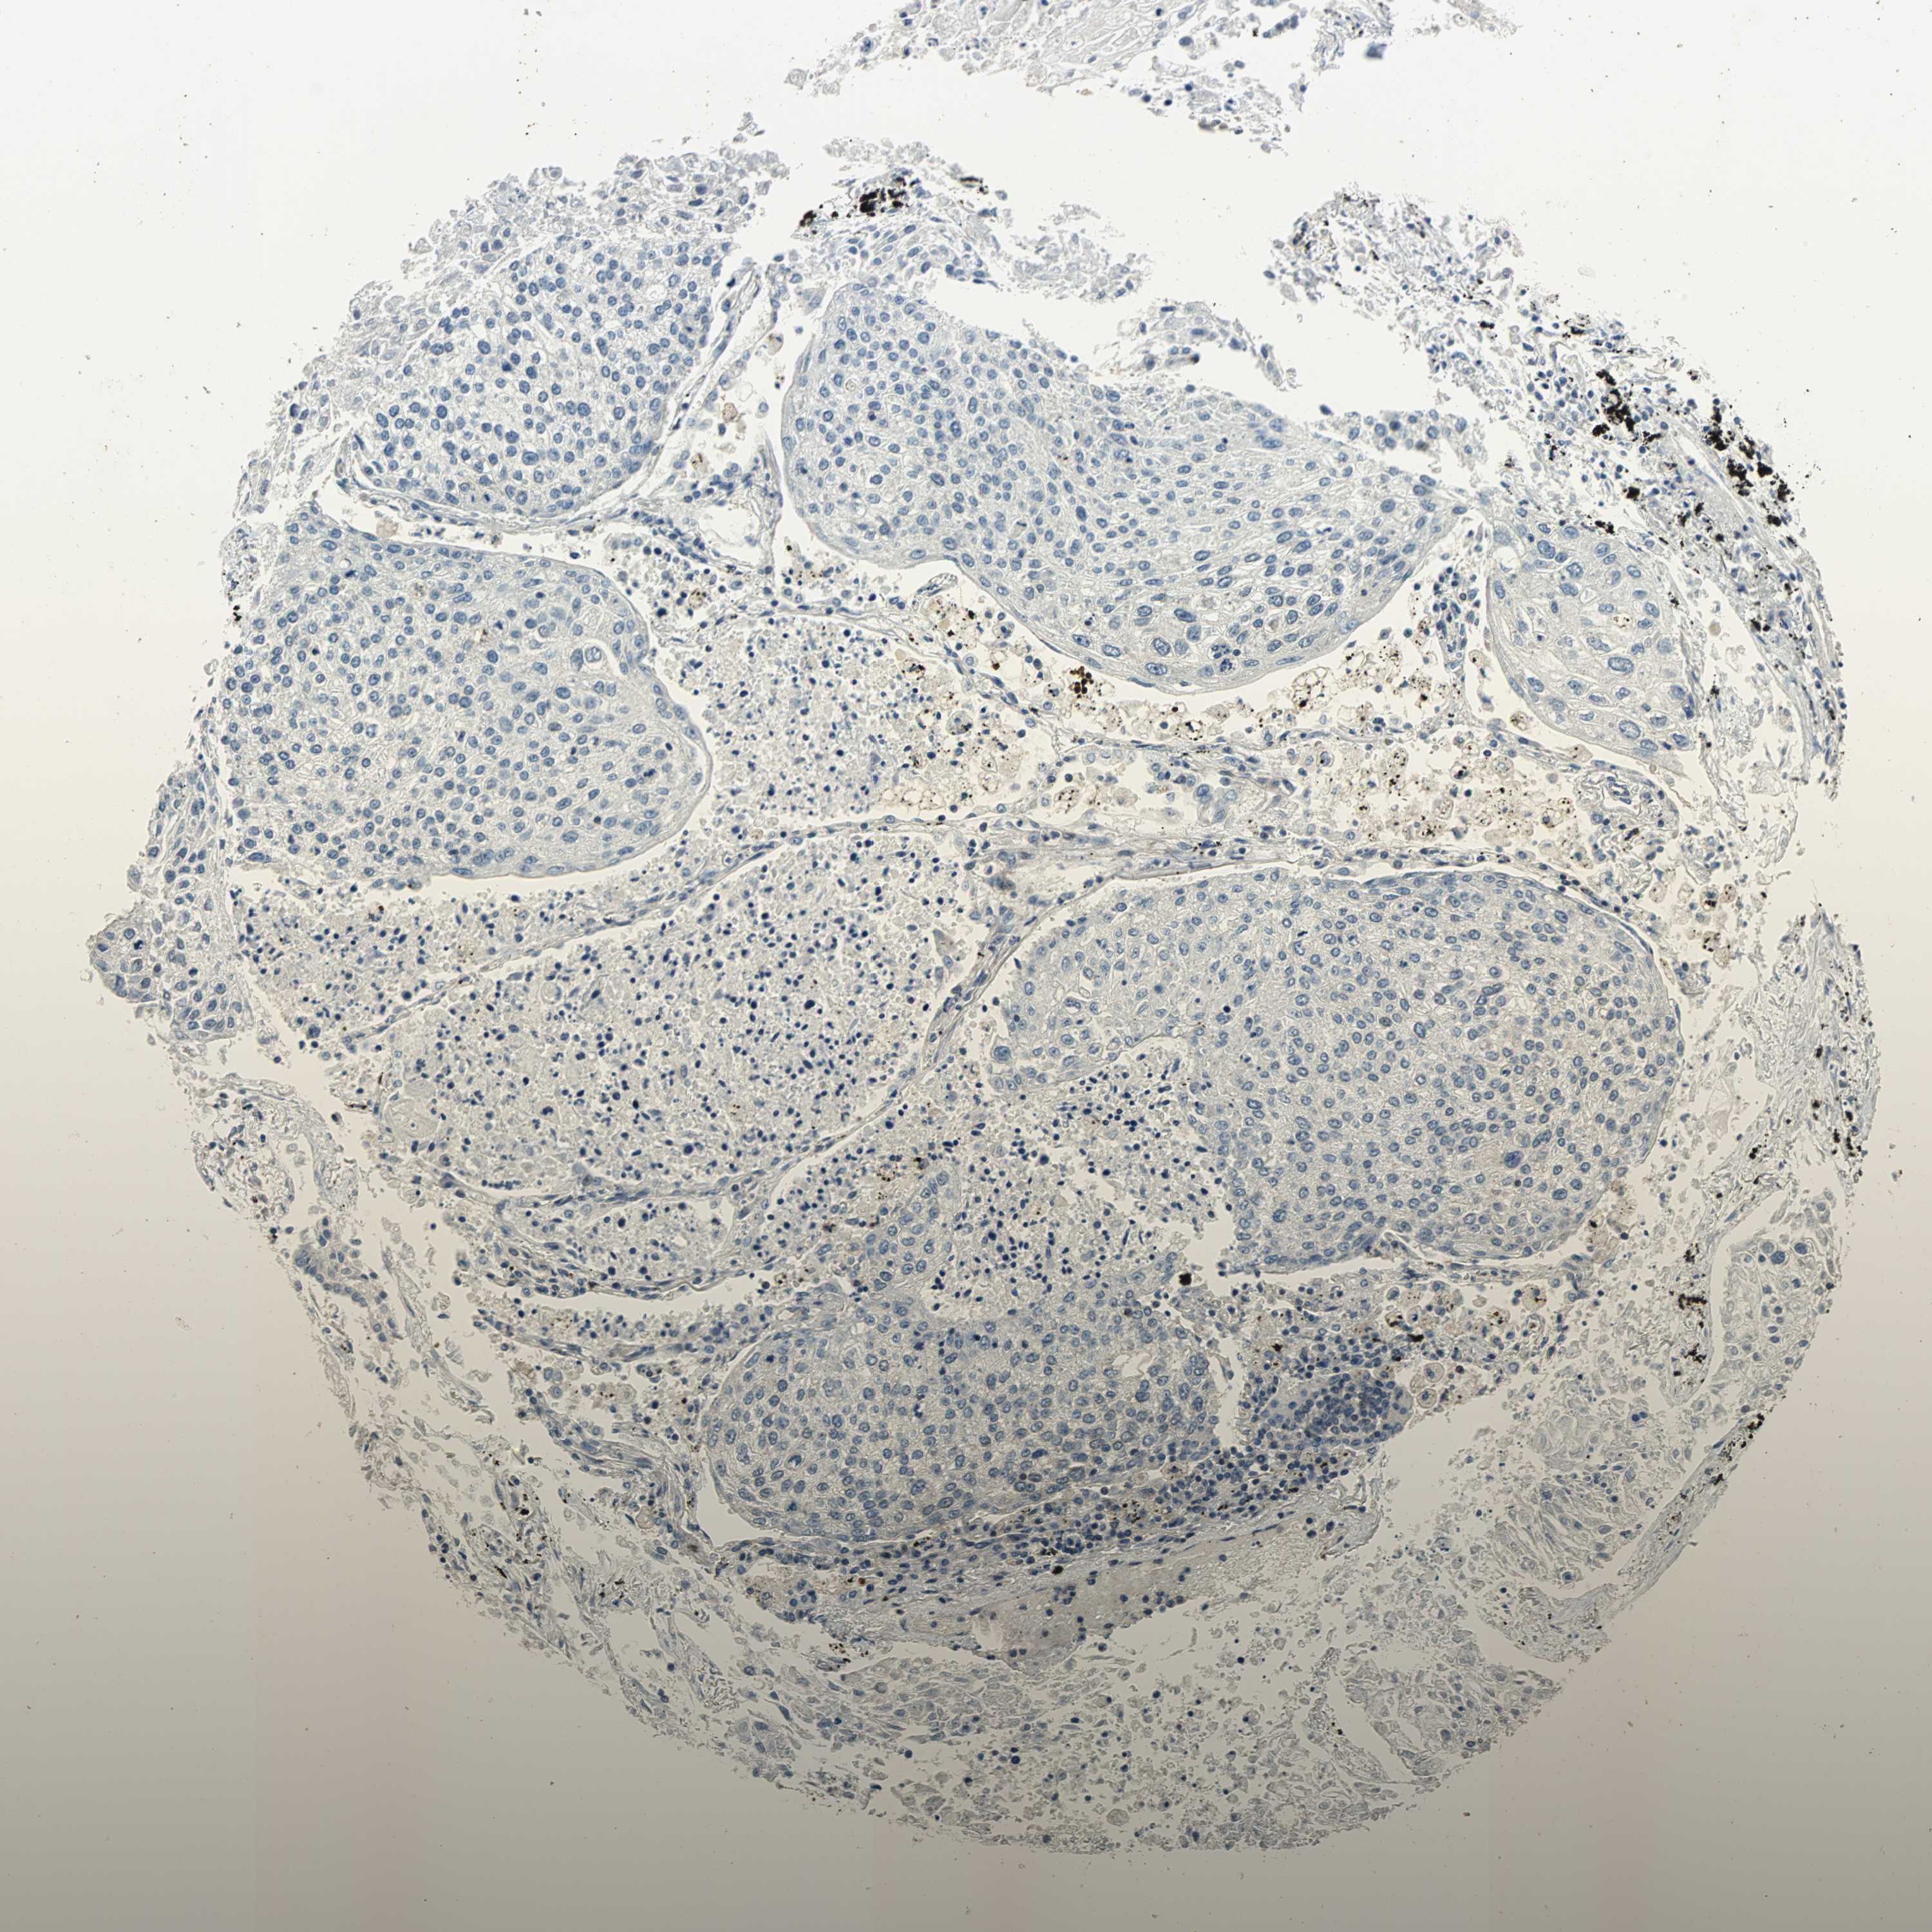

CANCER LUNG CANCER Show tissue menu

LUAD TCGA LUAD VALIDATION LUSC TCGA LUSC VALIDATION PROTEIN LUAD CPTAC PROTEIN LUSC CPTAC PROTEIN EXPRESSION

ANTIBODIES

AND

VALIDATION